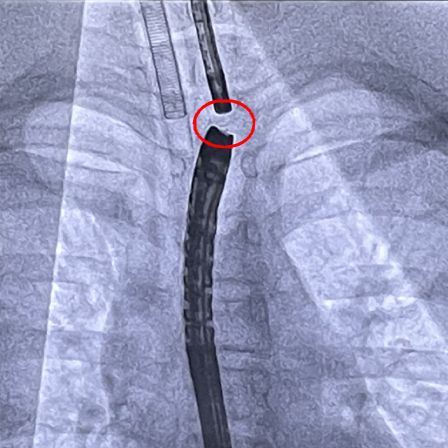

经过紧张而快速的筹备工作,2023年12月,莫绪明教授的MDT团队为小智进行了第一次胃镜检查和治疗。术中医生经胃造瘘口放入内镜,发现贲门开口狭窄,注入造影剂后透视显示贲门以上食管有10cm长的狭窄段,直径只有3-5mm。医生又对下段食管进行了扩张,扩张后胃镜进入病变食管可见下段食管形成盲袋样结构;经口胃镜检查中发现上段食管也同样有个盲袋;透视检查发现,上下段“盲袋”距离很短。

莫绪明教授和范志宁教授的MDT手术团队第一次讨论决定,小智的情况可以采用比“磁石压榨”技术创伤更小的穿刺支架技术恢复食道的通畅。两周后,团队为小智进行了第二次手术。医生再次扩张食管下段并将胃镜置于下段盲袋中,经口胃镜则置于上段盲端。在造瘘口胃镜监视下经口胃镜置入黏膜穿刺针,于盲端穿刺进入下段食管,沿穿刺孔放入导丝,在完成球囊扩张后,置入了由该院自主研发定制的全覆膜支架进行支撑,至此手术顺利完成。